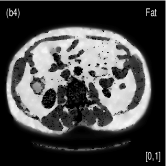

We also evaluated the proposed PWLS-TNV- method using clinical pelvis data. The patient’s pelvis data was acquired by Siemens SOMATOM Definition flash CT scanner using DECT imaging protocol. Table 4 lists acquisition parameters in the pelvis data scan. Fig. 5 shows the high- and low-energy CT images of the pelvis data. Fig.5 (b) shows selected basis materials, bone, iodine, muscle, fat and air, and their assosicated ROIs highlightened in white dashed line circles. We implemented the Direct Inversion method in mendonca2014a and used its results as the initialization for the PWLS-EP-LOOP xue2017statistical and the proposed PWLS-TNV- method. Fig. 6 shows the decomposed material images by the Direct Inversion, the PWLS-EP-LOOP and the PWLS-TNV- method. Table 5 summarizes the means and noise STDs of the decomposed material images by the above three methods. The volume fraction (VF) accuracies are , , and for the Direct Inversion method, the PWLS-EP-LOOP method and the proposed PWLS-TNV-, respectively. Compared with the Direct Inversion and PWLS-EP-LOOP method, the proposed method improves the VF accuracy by and respectively. The proposed PWLS-TNV- method decomposes basis material images more accurately, suppresses noise and decreases crosstalk, while retaining spatial resolution of the decomposed images compared to the other two methods.